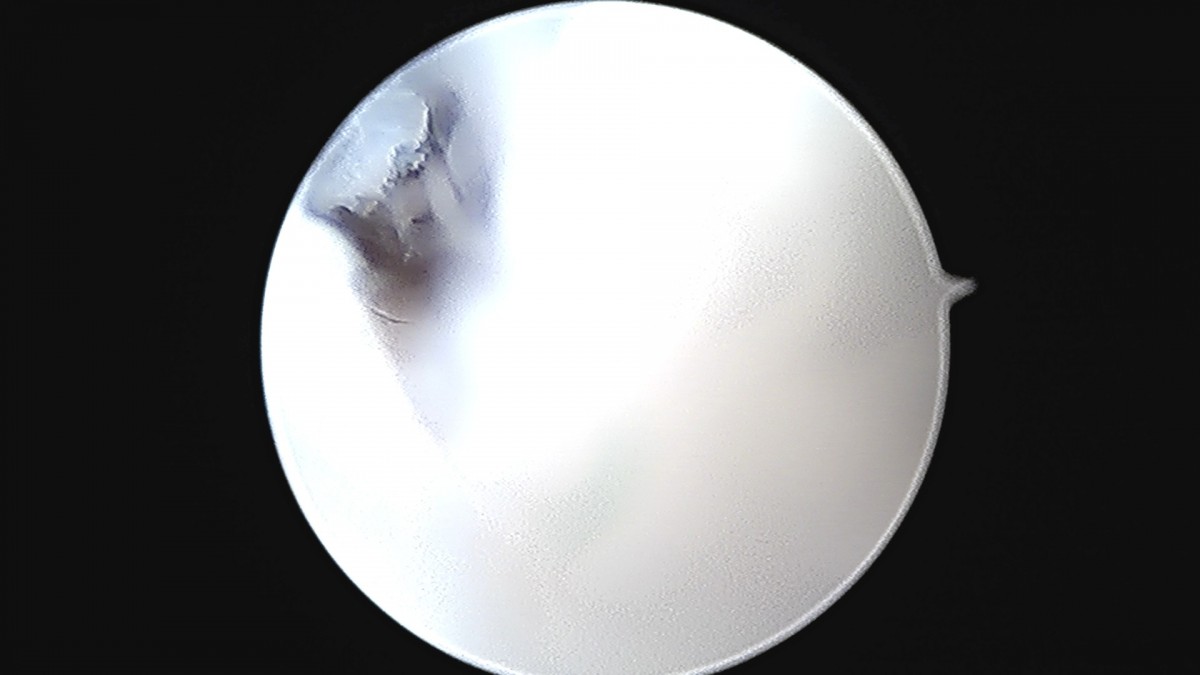

정지영원장님 발목 변연절제술 권공O 환자

작성자 최고관리자 댓글 0건 조회 743회 작성일 25-09-16 17:04